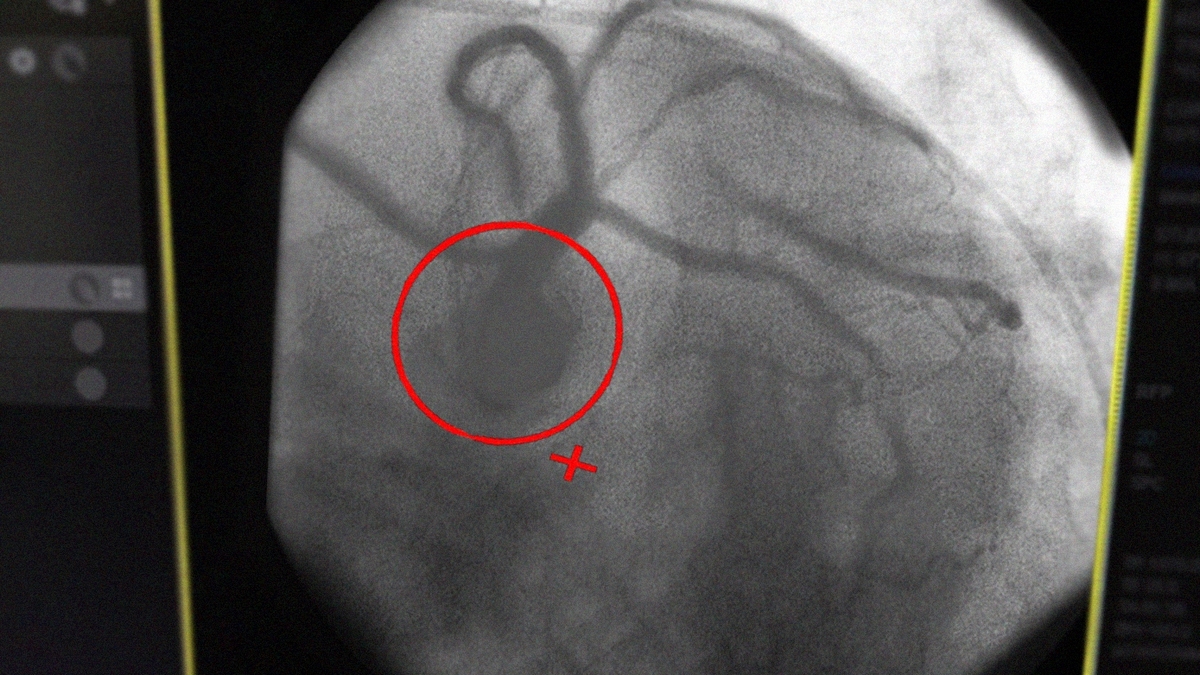

С утра 42-летний рязанец почувствовал себя плохо, однако все равно поехал на работу. За рулем он чуть не попал в ДТП – прохожие вызвали скорую помощь. В областной клинической больнице пациенту провели стентирование. Сейчас мужчина чувствует себя удовлетворительно, его выписали для наблюдения по месту жительства.

Фото: министерство здравоохранения Рязанской области